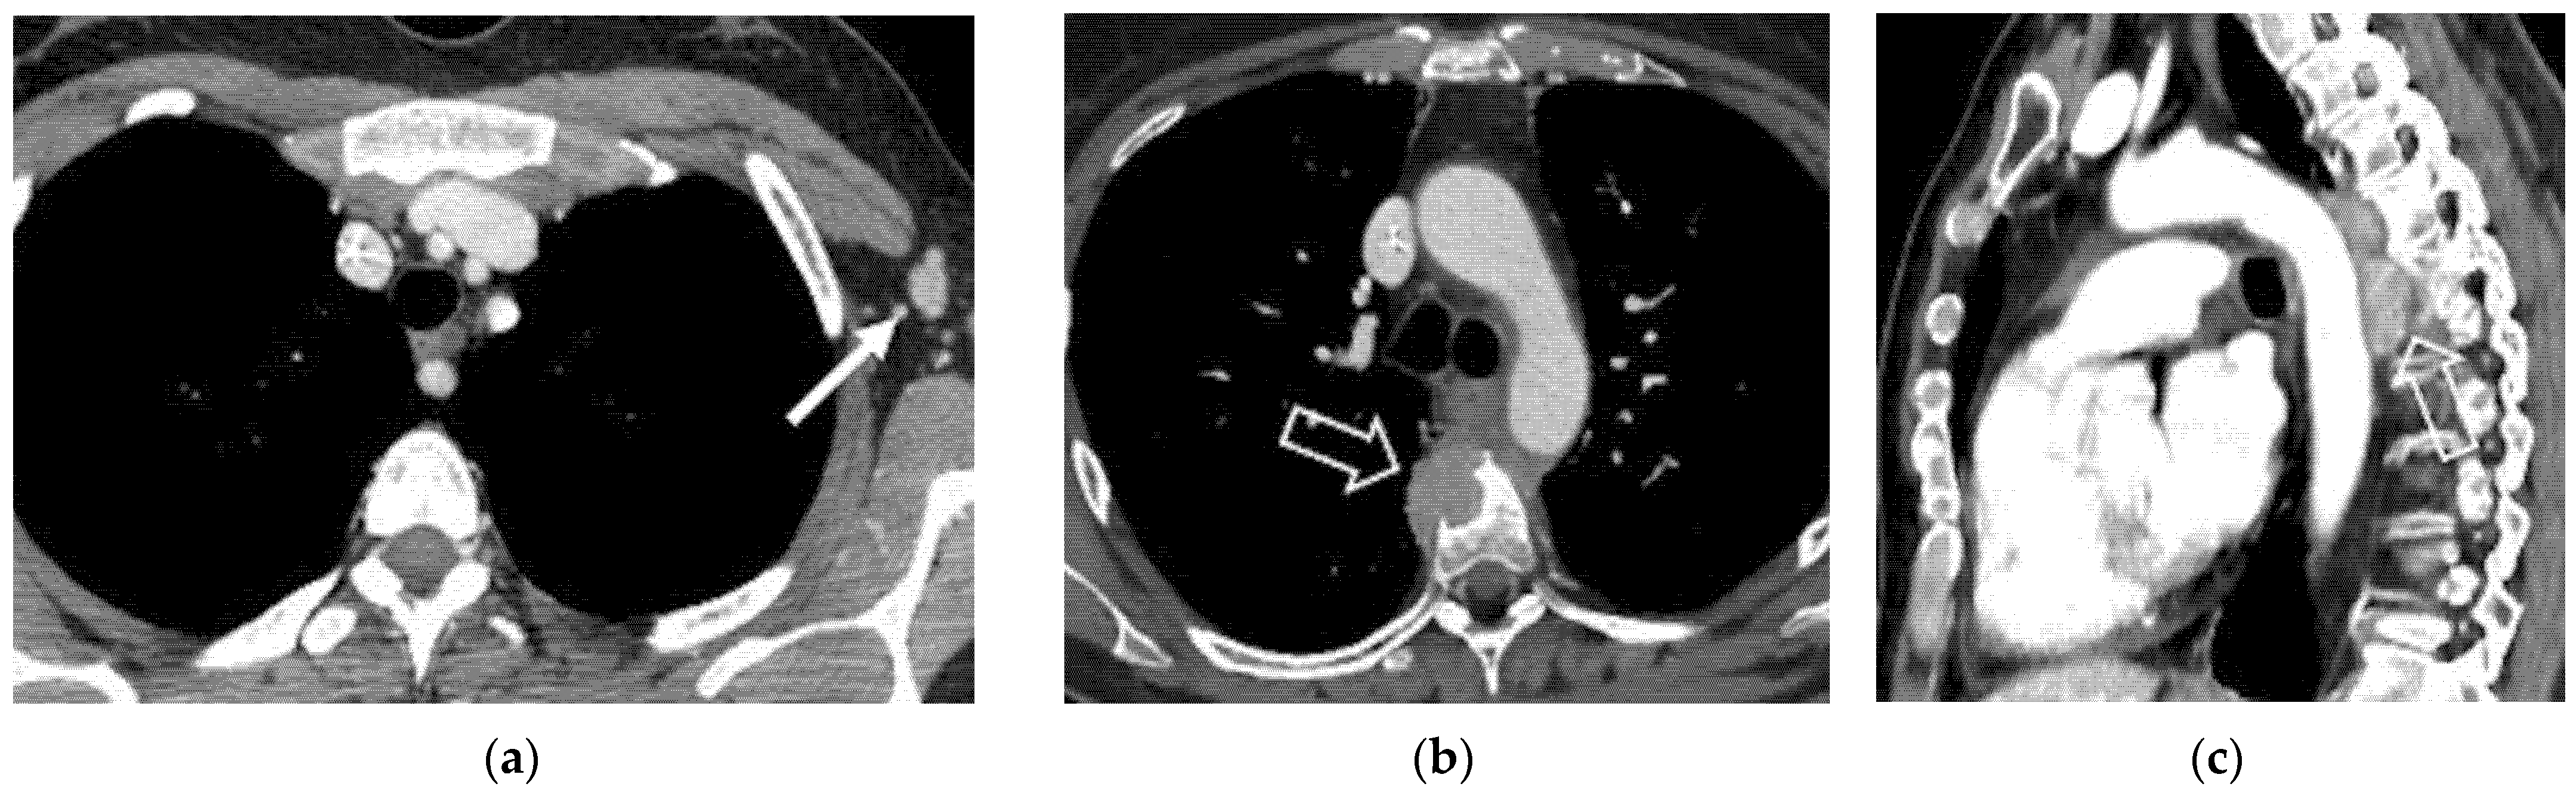

6.1. Supra-Diaphragmatic Lymph Nodes

| Supra-diaphragmatic lymph nodes |